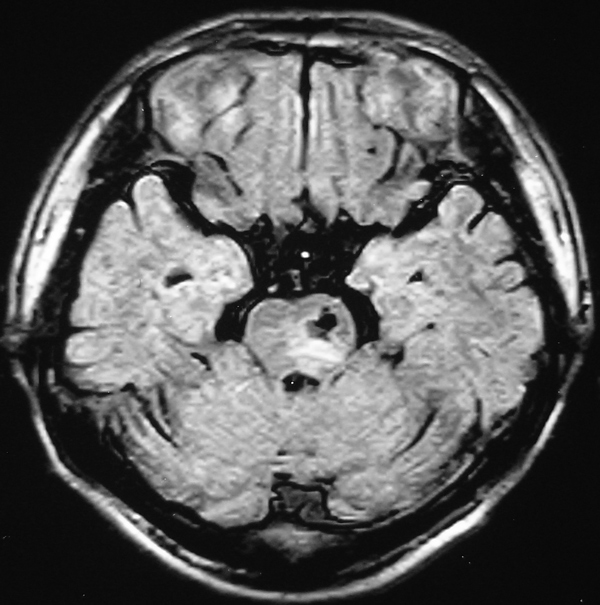

男 49岁 脑干腔隙梗塞5年。

这患者脑干(脑桥)腔隙脑梗塞是肯定的 有20002年资料 明天上传全部资料(当时工作忙 来不及)

图片质量不是很好!脑干偏左侧隐约可见低密度病灶,不知5年前怎样?单存本例支持:脑干梗塞!

1 单纯此图像定脑干梗塞依据不足. 2 可薄扫或核磁检查.

楼主是想具体分清是发生于脑桥还是中脑吧,脑桥的主要特征是结构就是小脑脚及四脑室,可以看到小脑脚及四脑室时就肯定是脑桥,中脑的主要特征就是环池,有完整的环池就是中脑,并且由于中脑短,一般只有一层可见,最多出现两层,本例层面应该是属于中脑层面,其上方应该是四叠体池及丘脑下部了.

楼主是想具体分清是发生于脑桥还是中脑吧,脑桥的主要特征是结构就是小脑脚及四脑室,可以看到小脑脚及四脑室时就肯定是脑桥,中脑的主要特征就是环池,有完整的环池就是中脑,并且由于中脑短,一般只有一层可见,最多出现两层。

不知小脑脚交叉到底另何指?中脑的病灶,应该和中脑导水管加以区别。

脑干梗塞在ct上是斑点状低密度,一般只能在桥脑或中脑才能显示,延髓是很难发现(伪影多)。mr上脑干梗塞应该是长t1长t2的斑点状表现。弥散能够发现早期梗塞灶,表现高信号。

①四脑室,脑桥平面有四脑室,中脑没有;

②环池:中脑平面有完整的环池,即前有脚间池、后有四叠体池。这是标准的om线扫描图像,如果不按om线扫描就有所变化;而桥脑没有完整环池,它前方是桥前池。

③三脑室,只要扫描基线偏移不大,看到三脑室出来同层面应该是中脑